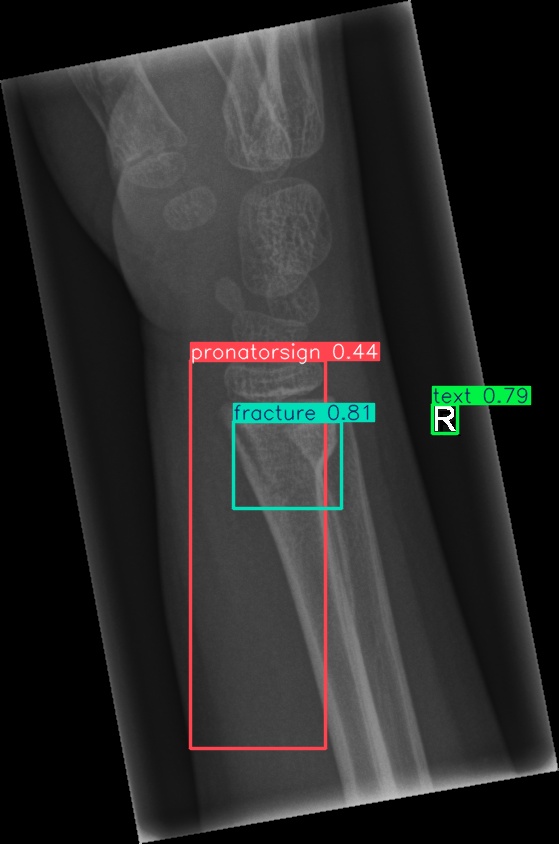

Figure 8: Sample of five images from the GRAZPEDWRI-DX test set, displaying ground-truth and predicted bounding box annotations: (a-e): ground-truth annotations, (f-j): YOLOv11l annotations, and (k-o): G-YOLOv11 annotations.

Table 4: Confidence scores predicted by YOLOv11l and the proposed G-YOLOv11l detectors for five images from the GRAZPEDWRI-DX test set, PR: pronator sign, FP: False positive.

Figure number Class name Confidence score predicted Confidence score predicted

by YOLOv11l by our G-YOLOv11l

8(a) soft tissue, fracture, metal, text -, 0.670.67, 0.860.86, 0.830.83 -, 0.700.70, 0.890.89, 0.840.84

8(b) fracture, text 0.780.78, 0.710.71 0.790.79, 0.730.73

8(c) fracture, text 0.820.82, 0.780.78 0.810.81, 0.790.79, (FP: pr 0.44)0.44)

8(d) fracture, fracture, text 0.770.77, 0.700.70, 0.880.88 0.760.76, 0.520.52, 0.890.89

8(e) fracture, periosteal reaction, text 0.760.76, 0.690.69, 0.760.76 0.750.75, 0.600.60, 0.760.76

The results in Table 4, derived from Figure 8, compares the confidence scores predicted by YOLOv11l and G-YOLOv11l detectors for five test images from the GRAZPEDWRI-DX dataset. Figure 8 contrasts ground-truth annotations with predictions from YOLOv11l and G-YOLOv11l. G-YOLOv11l shows slight improvements, such as higher confidence scores for "fracture" and "metal" in Figure 8(a) (0.700.70 and 0.890.89 vs. 0.670.67 and 0.860.86) and for "text" in Figure 8(b) (0.730.73 vs. 0.710.71). However, limitations include false positives, such as for "pronator sign" in Figure 8(c) (score 0.440.44), and lower confidence for some instances, as seen in Figures 8(d) and 8(e). While G-YOLOv11l demonstrates competitive performance, further refinements are required to improve its robustness.